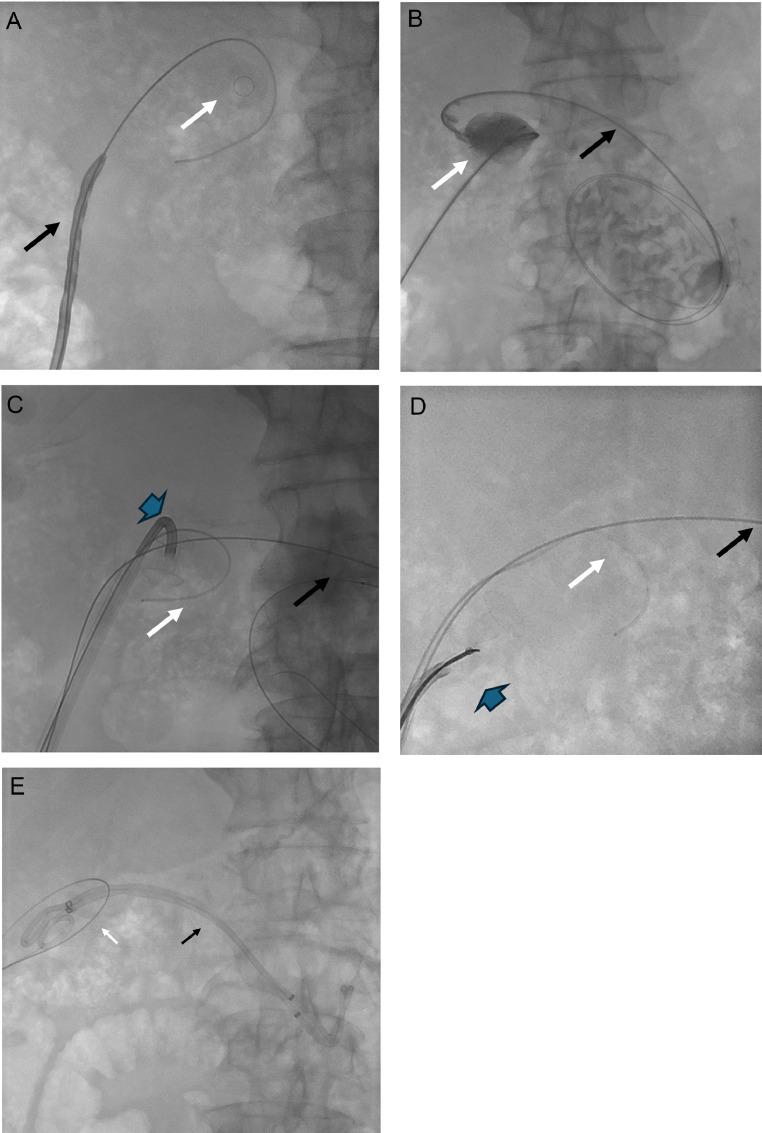

经皮内镜引导下对一名急性胆囊炎患者进行胆囊管腔内金属支架取出、碎石及胆囊十二指肠支架置入术。

Percutaneous endoscopy-guided gallbladder lumen-apposing metal stent retrieval, lithotripsy, and cholecystoduodenal stenting in a patient with acute cholecystitis.

Endoscopic ultrasound-guided gallbladder drainage (EUS-GBD) with lumen apposing metal stent (LAMS) has emerged as an effective alternative to percutaneous cholecystostomy in managing acute cholecystitis patients with contraindications to open or laparoscopic cholecystectomy. Herein, the authors describe a case of a 69-year-old male who presented to interventional radiology with sepsis due to acute calculous cholecystitis and LAMS migration into the gallbladder. After stabilizing the patient with percutaneous cholecystostomy, percutaneous cholecysto-lithotripsy/lithectomy, cholecystoduodenal stenting, and LAMS retrieval were performed. This report highlights the potential complications associated with EUS-GBD with LAMS insertion and contributes to the limited literature on percutaneous management of migrated LAMS.

内镜超声引导下胆囊引流术(EUS-GBD)联合管腔贴附金属支架(LAMS)已成为在管理有开腹或腹腔镜胆囊切除术禁忌证的急性胆囊炎患者时,经皮胆囊造瘘术的一种有效替代方法。在此,作者描述了一例69岁男性患者,因急性结石性胆囊炎伴脓毒症就诊于介入放射科,且LAMS迁移至胆囊。在通过经皮胆囊造瘘术使患者病情稳定后,进行了经皮胆囊碎石术/取石术、胆囊十二指肠支架置入术以及LAMS取出术。本报告强调了与LAMS置入的EUS-GBD相关的潜在并发症,并为关于迁移LAMS的经皮处理的有限文献做出了贡献。